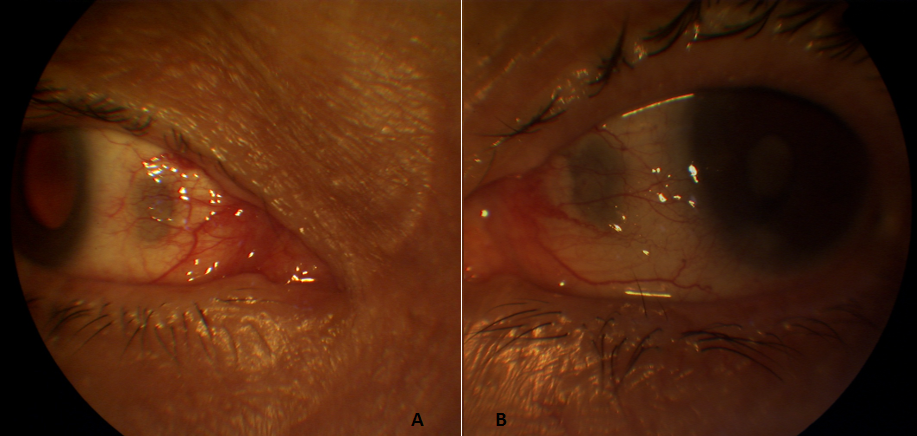

Plaques sclérales séniles

Nous rapportons le cas d'une femme âgée de 75 ans, hypertendue sous traitement, pseudophake au niveau de l'œil droit, cataracte de l'œil gauche et chez qui l'examen ophtalmologique décèle de façon bilatérale et symétrique des zones de dépression sclérale de couleur grisâtre située en avant de l'insertion des deux muscles droits internes. La plaque sclérale est le résultat d'une dégénérescence de la sclère liée à l'âge et est habituellement asymptomatique. La zone sclérale touchée devient mince et légèrement déprimée. Les lésions sont décrites comme étant bilatérales, symétriques, bien définies et de forme ovoïde. Elles sont habituellement situées en avant de l'insertion des muscles droits internes.